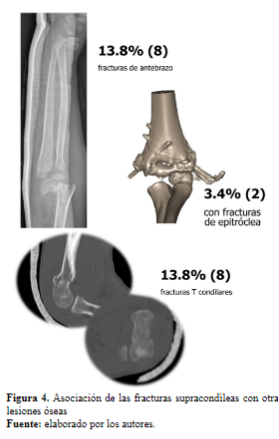

El 98.2% correspondió a fracturas en extensión, y el 1.8% en flexión; se asoció a un 13% con fracturas de antebrazo, 13.8% fracturas T condilares, 3.4% con fracturas de epitróclea (Figura 4), y en un solo caso se presentó con fractura de antebrazo y cóndilo lateral.

2. La asociación de las fracturas supracondíleas con otras fracturas como la de radio distal, intercondíleas y fracturas de epitróclea fue más común de lo que se esperaba.

Las fracturas supracondíleas de húmero se asociaron, principalmente, a fracturas de antebrazo, en especial de radio distal, y en igual proporción se relacionaron con las fracturas que tenían extensión condilar, también llamadas fracturas T condilares, que tienen una connotación distinta a una fractura supracondílea simple. De los 8 casos reportados la mitad se manejó con reducción abierta y la otra mitad con reducción cerrada, en estos casos la recomendación es lograr una reducción anatómica de la superficie articular para mitigar las complicaciones como el cúbito varo, pseudoartrosis y deformidad en cola de pescado (16-18).